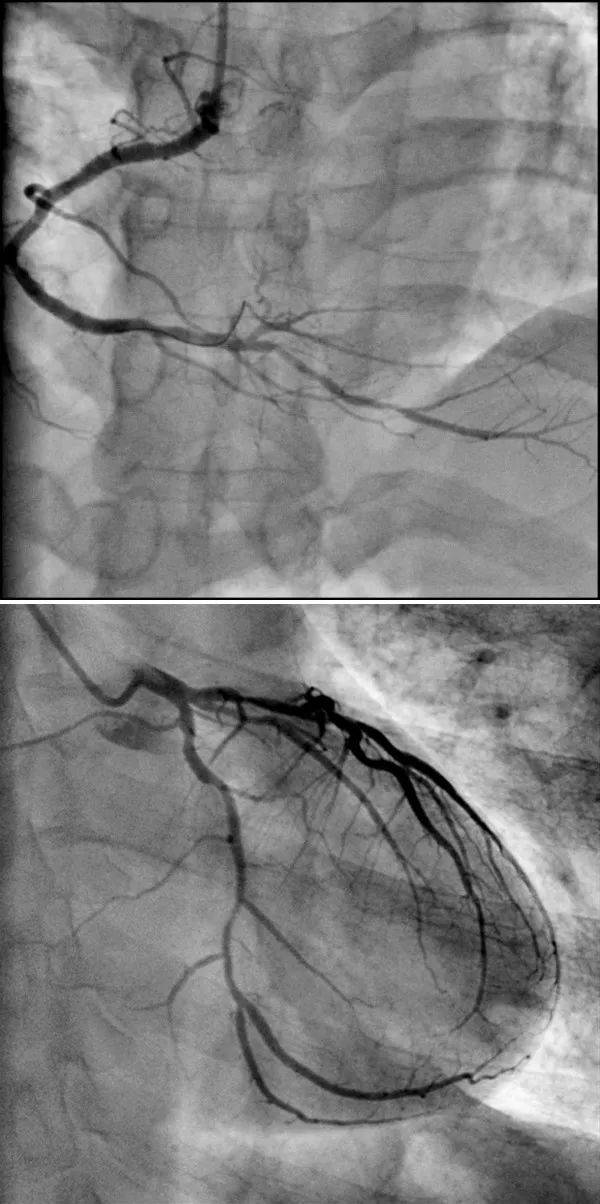

[经验交流]后交通动脉瘤一些dsa图片

右侧颈内动脉dsa(正常)